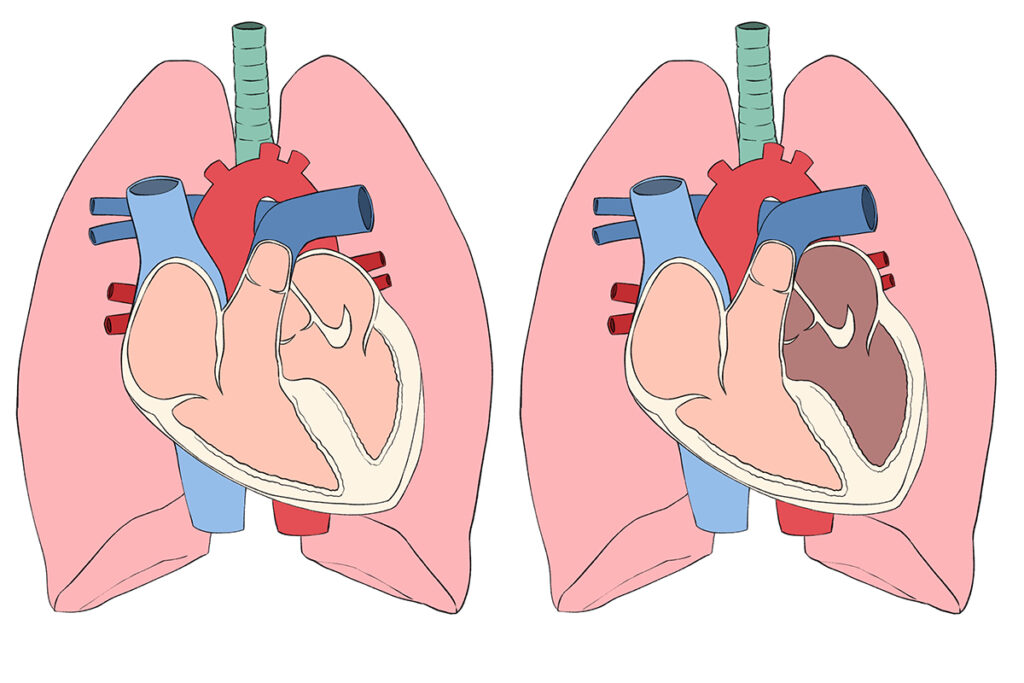

わんちゃんの⼼臓は、右⼼房/右⼼室・左⼼房/左⼼室という4つの部屋からできていま

す。それぞれの間には⾎液が逆流しないように「弁」があります。そのうち、左⼼房と

左⼼室を隔てているのが「僧帽弁」です。

粘液腫様僧帽弁疾患とは、この僧帽弁がしっかり閉まらなくなり、⾎液が逆流してしま

う病気です。初期には症状が出ないこともありますが、進⾏すると⼼臓が⼤きくなり、

疲れやすい・咳が出る・呼吸が速くなるといった症状があらわれます。

さらに悪化すると、肺⽔腫(肺に⽔が溜まる状態)を起こし、陸にいながら溺れているよ

うな⾮常に苦しい状態になることもあります。